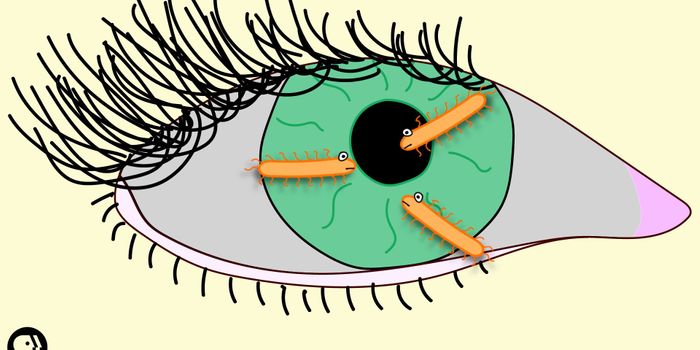

OCT 08, 2017VideosIn 2014, a woman in Taiwan lost her eyesight completely due to a parasitic infection caused by leaving in her contacts f ...